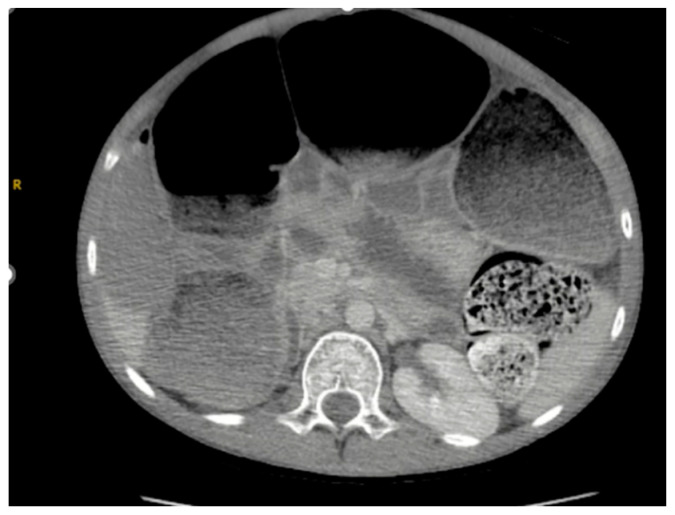

Background and Clinical Significance: Acquired myenteric hypoganglionosis is a rare dysmotility disorder that can present in childhood and adulthood, characterized by a reduced number of ganglion cells within Auerbach's plexus. Due to the rarity of the pathology, few case reports of acquired myenteric hypoganglionosis in adolescents have been described. This case report explores the presentation, risk factors, and surgical complications associated with the ultimate diagnosis of myenteric hypoganglionosis. Case Presentation: We present a case of a 12-year-old male with a history of constipation and achalasia, presenting with constipation and abdominal distention, who underwent a colonoscopy, which was converted to an exploratory laparotomy with loop ileostomy creation due to persistent significant abdominal distention. This was complicated by colonic perforation, most likely secondary to stercoral colitis, requiring takeback to the operating room on postoperative day 11 for an exploratory laparotomy with bowel resection and mucous fistula creation. The patient was then referred to Boston Children's Hospital for motility studies, which revealed poor colonic motility and plans to reassess motility in 1 year. Conclusions: Although rare, it is important to have high clinical suspicion for acquired myenteric hypoganglionosis in children, especially males, with severe constipation.